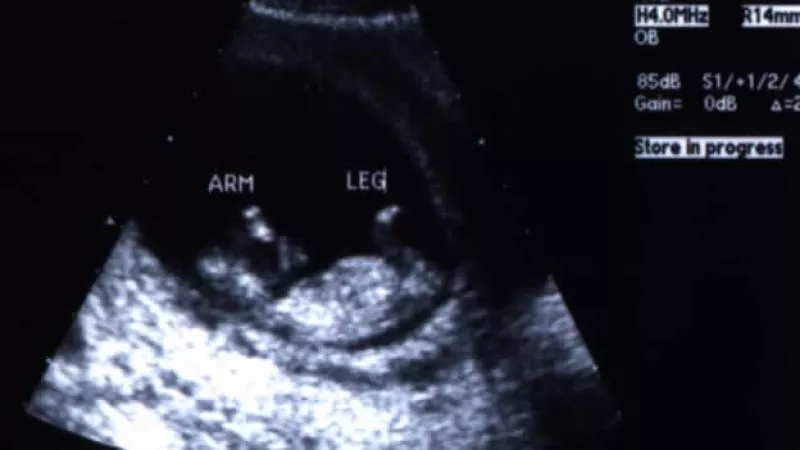

Los médicos de Texas deberán dar ecografías a mujeres que deseen abortar

Una corte federal avaló la legislación que establece que los médicos deberán brindar imágenes de un feto o embrión a quienes quieran abortar

Una corte de apelaciones federal de Estados Unidos determinó este viernes que el estado de Texas, en el sur del país, puede seguir adelante con la aplicación de una ley que exige a los médicos que entreguen una ecografía a las mujeres embarazadas que quieran practicarse un aborto.

La ley establece que las mujeres que quieran hacerse un aborto en Texas vean antes una imagen del embrión o feto y escuchen una descripción de su desarrollo antes de que inicie el procedimiento.

La ley señala que, al menos 24 horas antes de un aborto, una mujer debe realizarse una ecografía, un procedimiento que recurre a un ultrasonido para generar una imagen.

El médico debe dar, “en una manera entendible, una explicación verbal de los resultados de la ecografía, incluyendo una descripción médica de las dimensiones del embrión o feto, la presencia de actividad cardiaca y la presencia de miembros externos u órganos internos”, dice el texto.